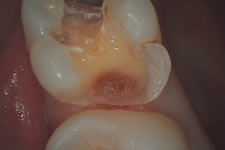

2000年に初めてFDI(国際歯科連盟)が提唱したMinimal Intervention(最小の侵襲)の概念は、現在、日本の歯科治療においても定着しつつあります。当クリニックでは、なるべく削らない・なるべく神経を取らない治療を心がけております。虫歯を大きく削って、大きな銀歯を被せる治療から、虫歯だけを削ってコンポジットレジン(白い充填物)を詰める治療にシフトしております。

プロルートMTA

諸外国では1998年以降様々な臨床応用が認められていますが、日本では2007年4月に覆髄材として販売をしました。 水酸化カルシウムに代わる直接覆髄に適したユニークなセメントです。 封鎖性が優れており、漏洩による炎症を引き起こすことなく外来刺激を遮断します。 これにより、従来の治療では歯の神経を取っていたケースも、高い確率で歯の神経を残す事が可能です。この治療法は保険外治療となります。 詳しくはクリニックにお問い合わせ下さい

症例紹介

術 前 術 中 術 後

オーキッド|虫歯治療② オーキッド|虫歯治療⑤ オーキッド|虫歯治療③ オーキッド|虫歯治療④ オーキッド|虫歯治療⑥